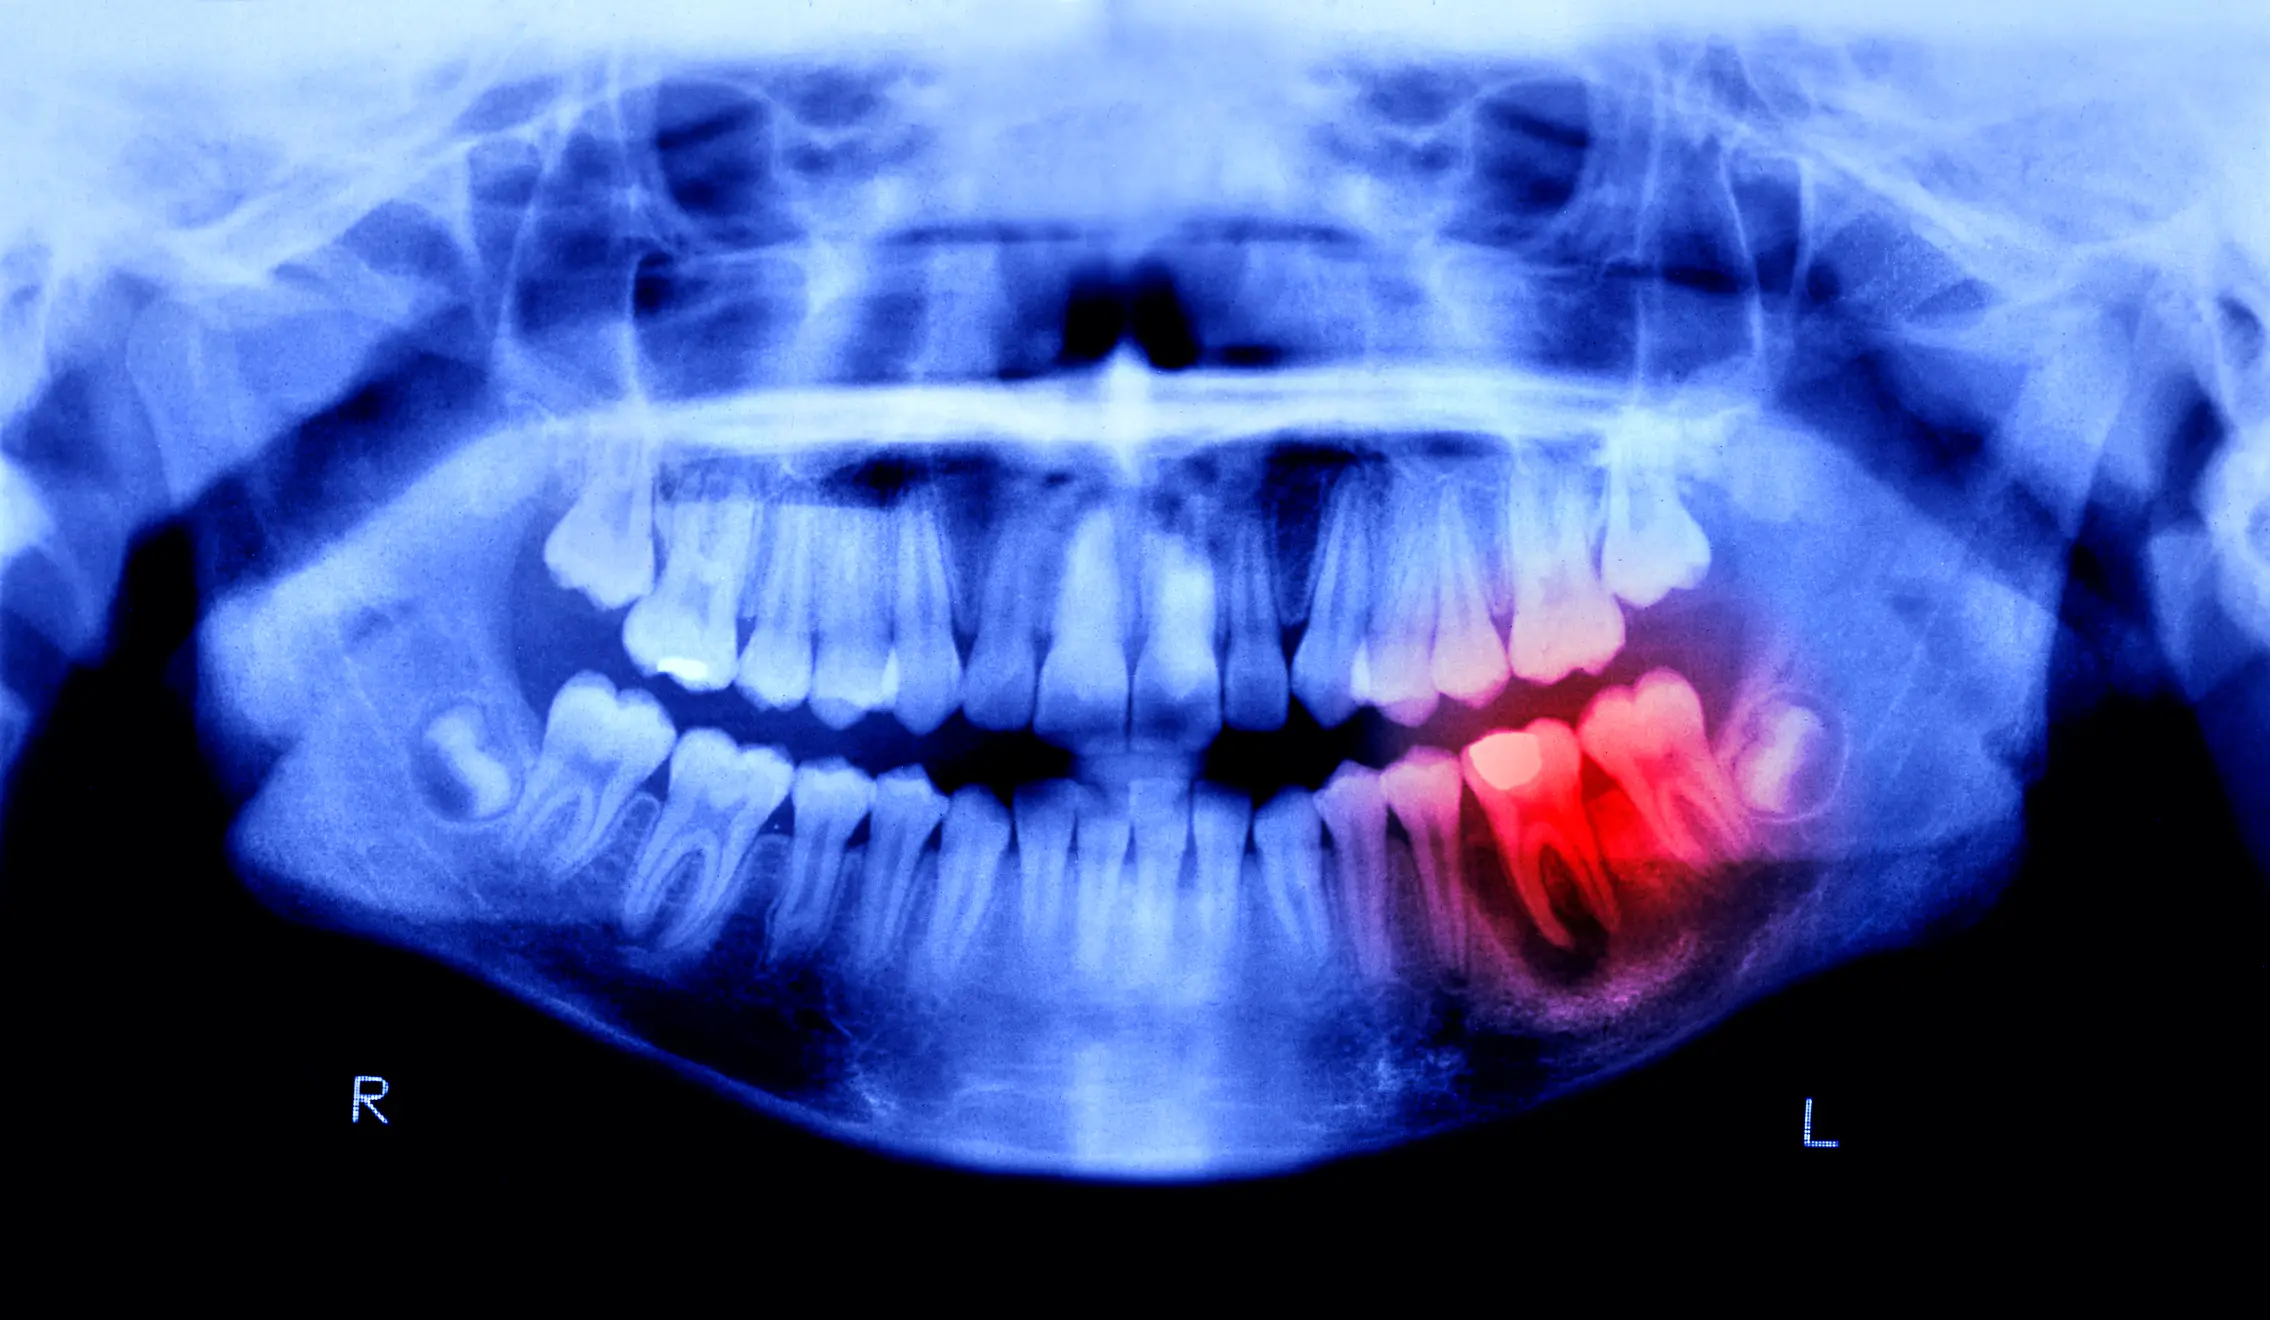

Loose or losing teeth

Losing teeth once you get past being a child is a worrying sign, and ultimately you should be keeping all your teeth once you get to adulthood. While losing them or having them feel loose can signal to your dentist that you have serious gum disease, it can also be a sign of your bone health too.

Research has shown there are links between osteoporosis and bone loss in the jaw, and if this decreases it can mean your teeth are more likely to fall out.